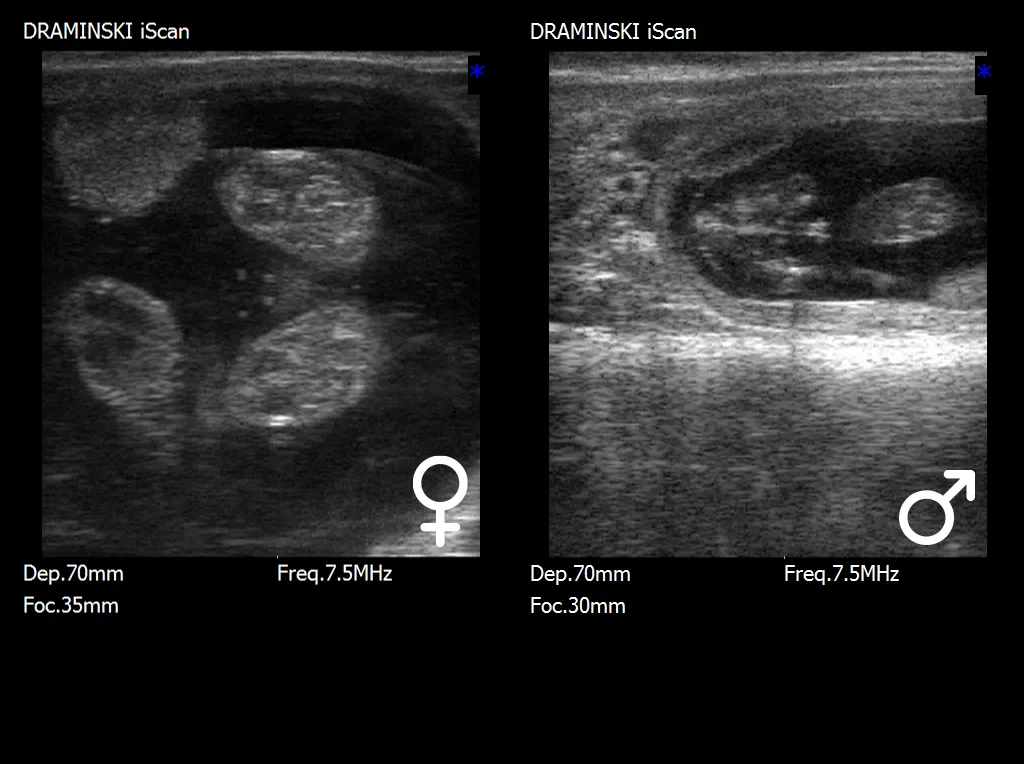

The optimal period for fetal sex determination is between days 55 and 70 of pregnancy.

At this stage, the key diagnostic structure is the genital tubercle (tuberculum genitale), which undergoes characteristic displacement depending on the fetus’s sex. In male fetuses, the genital tubercle shifts toward the umbilicus and the future penis, while in female fetuses, it is located closer to the tail, in the region of the future vulva. Correct interpretation of the tubercle’s position requires not only high-quality ultrasound imaging but also appropriate experience, as small variations in fetal positioning can influence the assessment.

In the later stages of pregnancy, after approximately days 70–80, identification of more developed external genital organs becomes possible, such as the scrotum in male fetuses or vulvar structures in female fetuses. Although sexual characteristics are more apparent at this stage, the examination becomes more challenging due to the increasing size of the fetus, its deeper position within the uterine cavity, and the limited maneuverability of the ultrasound probe.